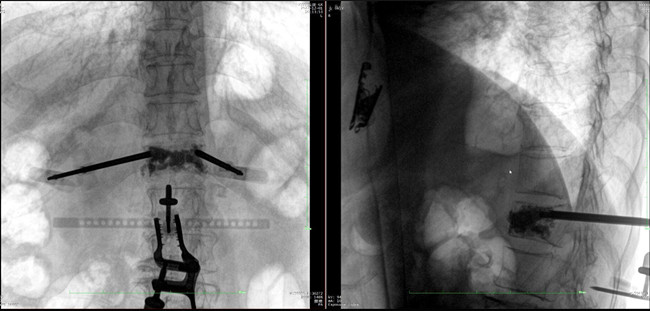

在病人體表切開一個長1-2cm的創口,沿骨科機器人的機械臂定位點方向將克氏針導向套筒,通過創口送至病灶椎體處,并沿套筒方向打入克氏針進行定位。沿導針插入工作套管,取出導針,完成球囊擴張后,通過骨水泥注入器準確地在骨折部位緩慢注入骨水泥,幫助其恢復椎體的形狀和強度。

*骨水泥置入效果良好